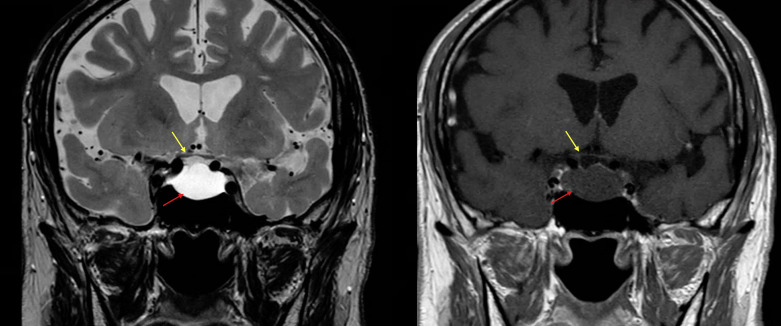

Case presentation: A 72-year-old man was incidentally found to have binasal OCT-GCIPL thinning during a routine eye examination. Visual acuity was 20/20 in both eyes. Pupils were equal and reactive without a relative afferent pupillary defect. His Humphrey 24-2 SITA-Fast visual field test results were normal. A magnetic resonance imaging (MRI) revealed a nonenhancing (cystic) sellar/suprasellar mass measuring 1.7 cm craniocaudal by 2.1 cm anteroposteriorly, without associated optic chiasm compression. The lesion was suspected to be either a cystic pituitary adenoma or a Rathke's cleft cyst. Follow-up examination 1 year later showed all findings remained stable, including an unchanged visual acuity, visual fields, OCT-GCIPL, and MRI.

Conclusion: The binasal thinning observed on OCT-GCIPL in this case, despite the absence of chiasmal compression on MRI, is suggestive of previous compression of the optic chiasm. This case highlights the potential for spontaneous regression of pituitary adenomas and underscores the importance of OCT-GCIPL as a vital tool for detecting optic chiasmal damage.